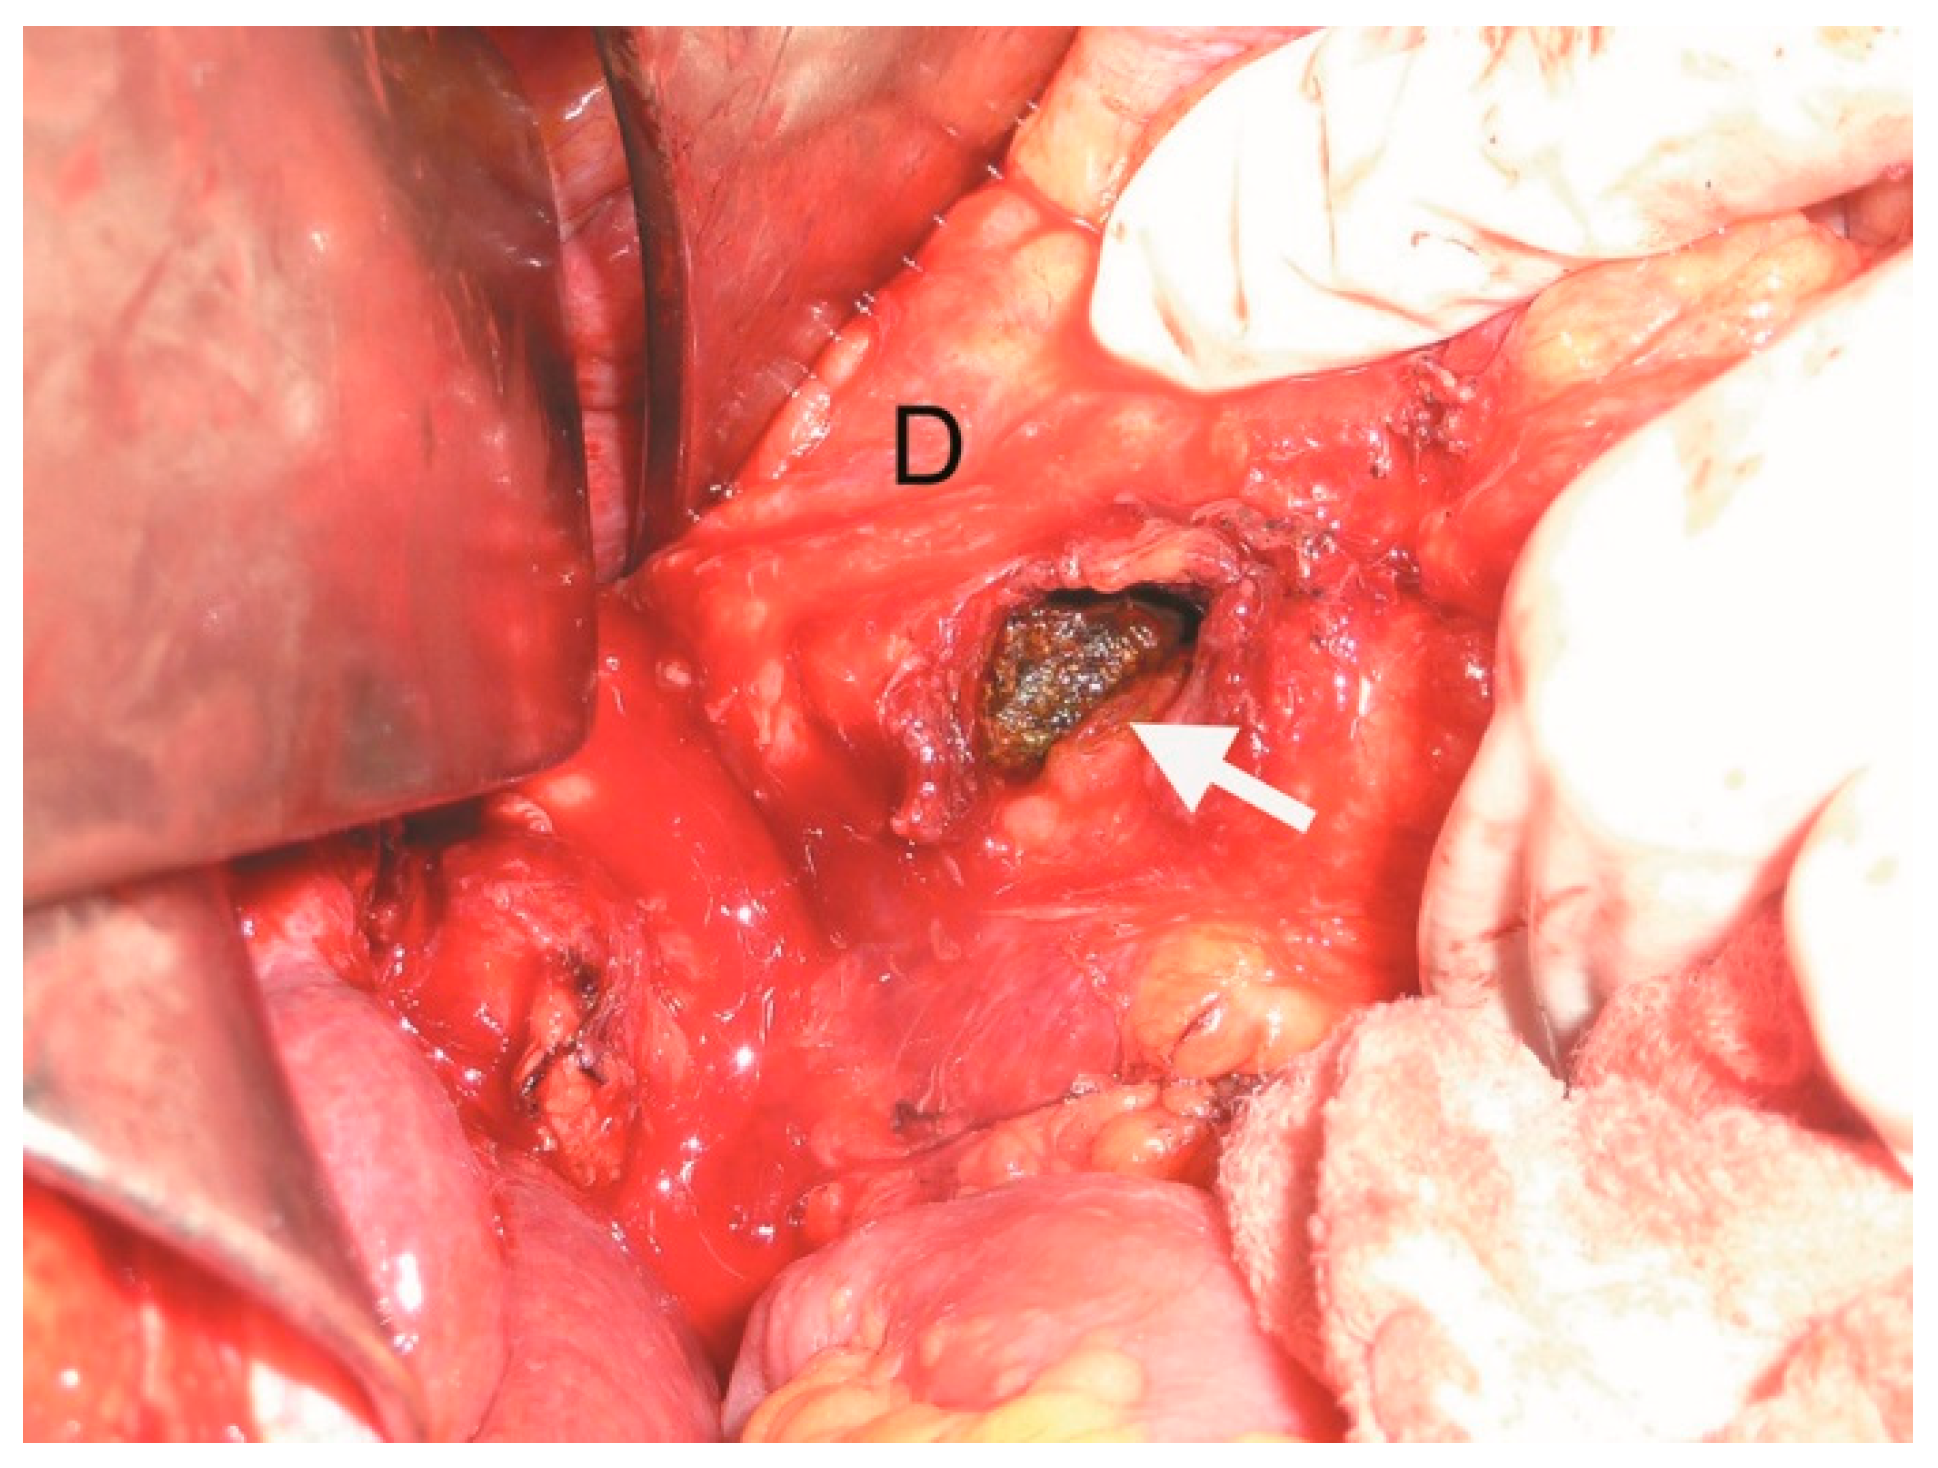

The patient was then taken to the operating theatre for exploratory laparotomy. Intraoperatively, significant chronic inflammation and adhesion between the gallbladder and the duodenum were noted. A cholecystectomy and repair of the cholecysto-duodenal fistula were performed through the orifice of the fistula corresponding to the duodenum. The duodenum was closed with separate sutures in two layers with synthetic absorbable suture (3-0 Vicryl®, Ethicon Inc., Raritan, NJ, USA). The small bowel distal to the stone was not dilated. The gallstone fragment removed from the duodenum measured 3.9 cm × 4.0 cm × 4.0 cm (Figure 3, Figure 4 and Figure 5).

Figure 3.

Intraoperative image showing duodenotomy (white arrow) with the impacted gallstone (D—duodenum).